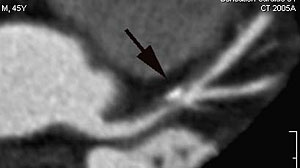

A long segment soft plaque with a calcific focus involving the LAD (black arrow). This was a 45-years old asymptomatic man with a strong family history of coronary artery disease. The rest of the coronary vessels were normal, except for the plaque involving the LAD. There was no significant stenosis, but the lesion was a strong motivator for the patient to make significant life style changes.